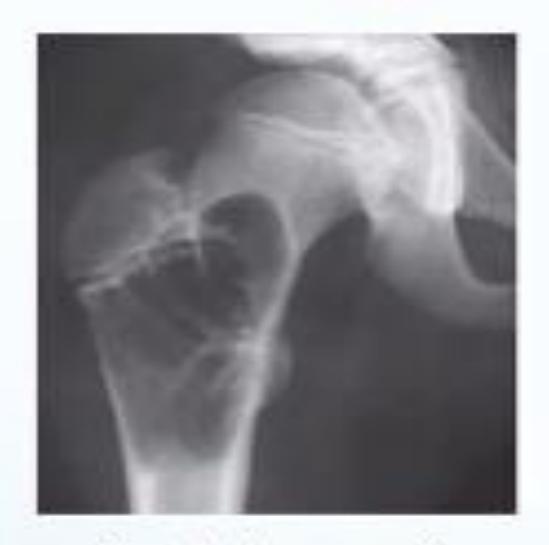

A 70-year-old inactive female presents to the emergency department after falling down in the bathroom. Sheโs been complaining from hip pain and inability to bear weight. Which of the following is the most appropriate choice of treatment?

- C. Bipolar hemiarthroplasty

Intertrochanteric Fracture

Diagnosis: Intertrochanteric fracture of neck of femur Treatment: Dynamic hip screw or proximal femoral nail

A 50-year-old male tripped over the edge of carpet at home. He heard a crack and is unable to walk. He gave history of progressive weight loss. On clinical examination, he was in pain with a deformity at upper right thigh. He looks pale.

What are the key x-ray findings?

- Decreased bone density in the right proximal femur

- Fracture in the neck of the femur

- AP view of the right proximal femur

What is the diagnosis?

- Pathological fracture due to osteoporosis